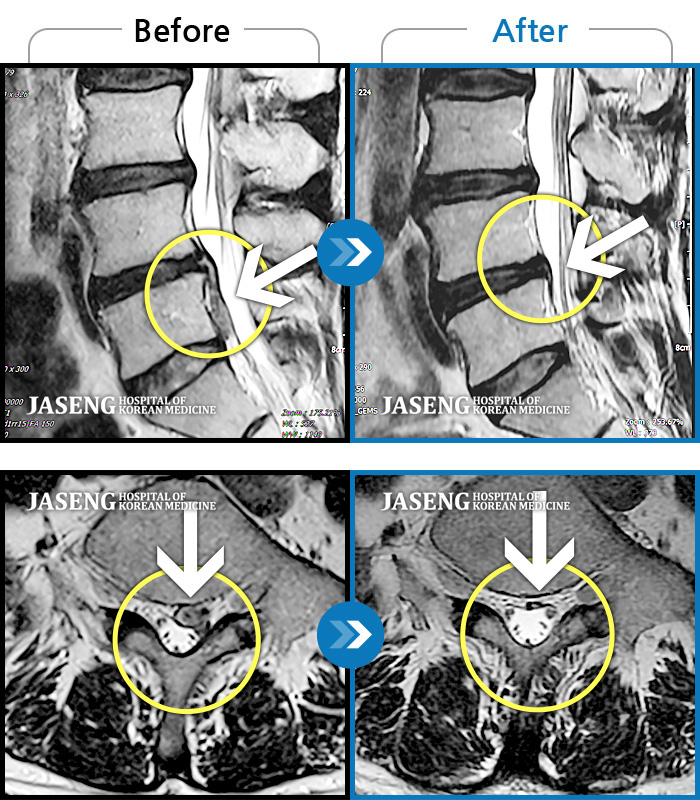

Before

After

환자에게 사전 동의를 받아 동일 조건에서 촬영되었습니다.

개인에 따라 치료 후 부작용이 발생할 수 있으니 의료진과 상담 후 치료를 진행하시기 바랍니다.

허리 양측 골반 통증, 보행 시 다리에 힘이 잘 안 들어가 절뚝 거림

좌측 골반 상연으로 통증과 좌측 대퇴부 통증이 있었다.